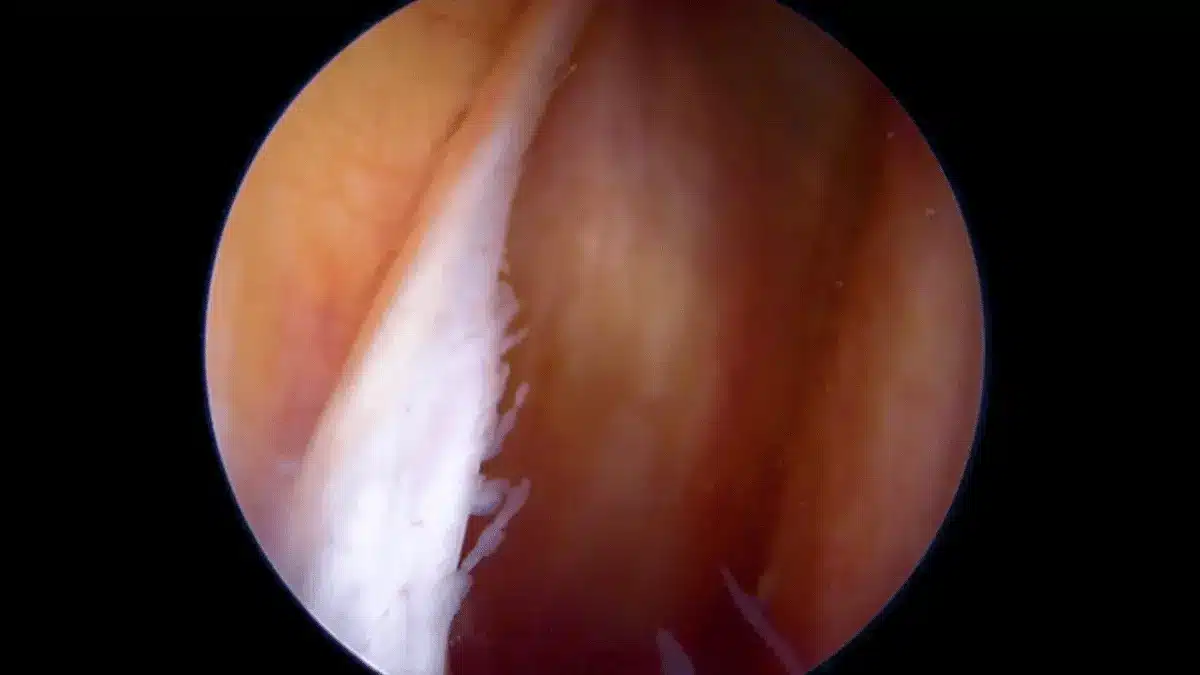

Cirurgia de artroscopia de joelho: indicações e recuperaçãoA artroscopia do joelho é uma cirurgia de pequena incisão que permite ver por dentro da articulação e tratar lesões… Leia mais »

Meniscectomia parcial: indicação, cirurgia e recuperaçãoA meniscectomia parcial serve para tirar só a parte do menisco que foi danificada, mantendo o máximo possível da estrutura… Leia mais »

Meniscectomia: quando operar o menisco e como recuperarUma dúvida recorrente entre meus pacientes é sobre o que é a meniscectomia. Então, é a cirurgia que remove a… Leia mais »

Sinovectomia no joelho: indicações e recuperaçãoA sinovectomia no joelho é um procedimento que busca remover a membrana sinovial inflamada, ajudando a preservar a articulação e… Leia mais »